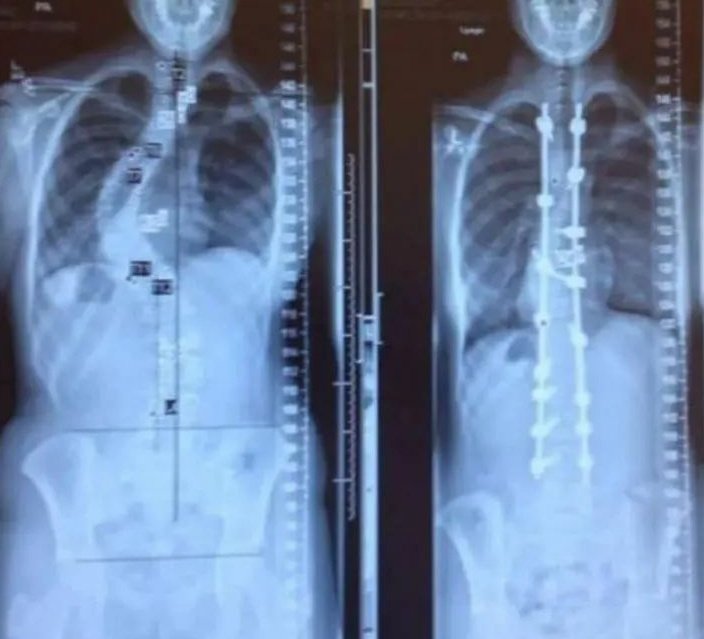

La Columna Vertebral de una persona antes y después de su operación de escoliosis. Image